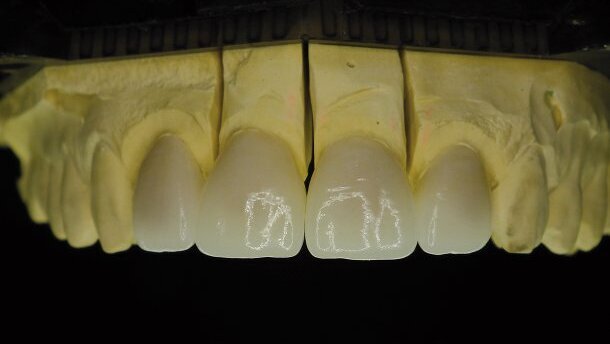

Les surfaces dentaires préparées étaient saines et présentaient une couleur naturelle sans aucune dyschromie, ce qui nous a permis d’utiliser le lingotin de matériau extrêmement translucide IPS e.max Press HT BL1 (Fig. 6). Les coiffes ont été pressées à partir d’un matériau à base de disilicate de lithium, et soumises à une cuisson dans un four spécial.

Étant donné le niveau esthétique extrêmement élevé exigé par ce cas, le céramiste a décidé que les quatre restaurations devaient être réalisées en utilisant la technique dite du « cut-back » (découpe du bord libre) sur les coiffes et les facettes pressées, afin de parvenir à un très haut degré d’individualisation, en utilisant les matériaux de préparation incisive de la gamme IPS e.max Ceram.